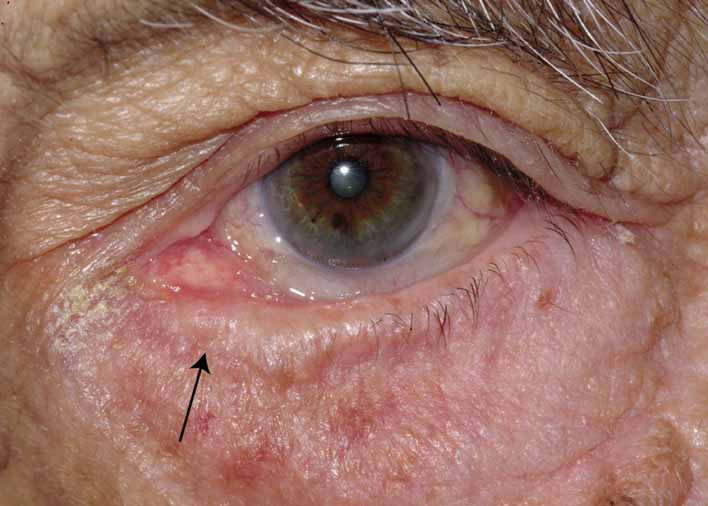

Punctal stenosis in the adult population is a common cause of epiphora

as previously discussed. Again, before proceeding with surgery, the surgeon

should be especially cautious of the older patient with a concominant

dry eye as increased tear outflow may further exacerbate the reflex

tearing. Several techniques are available to treat punctal stenosis. The

two recommended techniques are a punctoplasty and Silastic stenting. The

punctoplasty allows for controlled opening of the punctum. Typically

a two-snip procedure is performed. This is performed in

one of two ways. The first is to remove a V-shaped wedge from

the vertical portion of the puncta and canaliculus on the conjunctival

surface. This opens the most proximal portion of the system with out

risking damage or scarring to the remainder of the canaliculus. The second

two-snip procedure consists of a single vertical cut that

is created in the puncta and canaliculus followed by a single horizontal

cut along the proximal portion of the canaliculus. The concern with

these techniques is the potential damage to the canaliculus and its

function. If too much is cut, the canaliculus may not function properly. Also

there is a greater chance for scarring within the canaliculus

as it heals. To counterbalance the potential for scarring after the snip

procedure, a Silastic stent can be placed. The stent may also serve

the function of dilating and holding open the puncta and canaliculus

as the system heals. Overall punctoplasty and stenting can be quite helpful. If

the patient does not respond, however, consideration should

be given to some of the other functional problems such as the flaccid

canalicular syndrome. It may be useful to obtain dacryoscintigraphy in